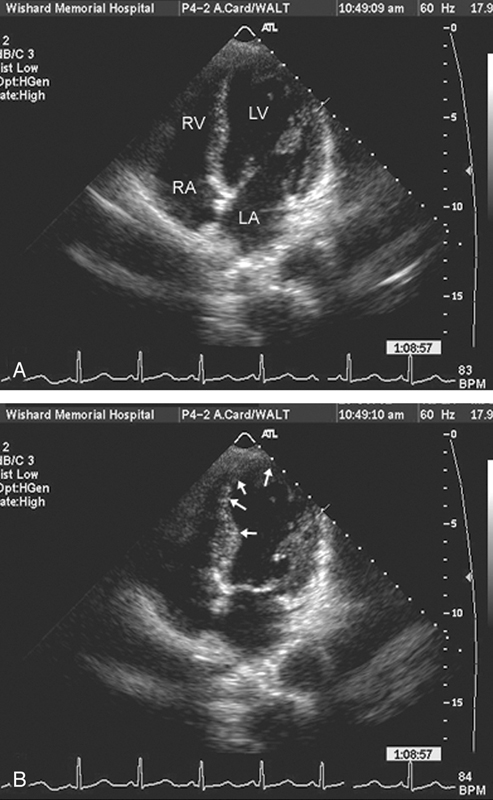

فحوصات تشخيصية لبعض امراض القلب والشرايين التاجية